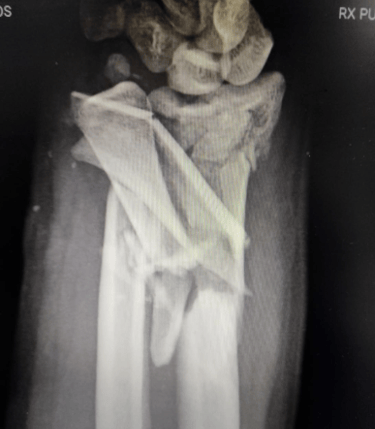

Fraturas e Luxações

Podem ocorrer na mão, punho ou antebraço por acidentes de trânsito, trabalho ou quedas. As mais comuns afetam os ossos da mão (metacarpos), dos dedos (falanges), antebraço (rádio e ulna) e punho (carpo).

O diagnóstico é feito com exames de imagem e avaliação clínica.

O tratamento pode ser conservador ou cirúrgico, conforme o tipo e a gravidade da lesão.